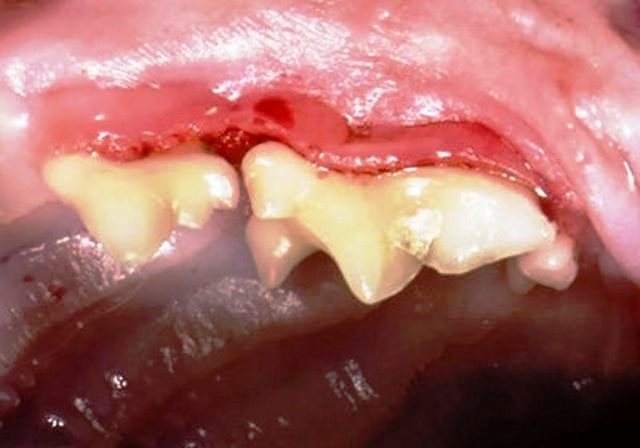

Дёсны (лат. Gingiva) — это слизистая оболочка, покрывающая альвеолярный отросток верхней челюсти и альвеолярную часть нижней челюсти и охватывающая зубы в области шейки. С клинической и физиологической точек зрения в десне различают межзубный (десневой) сосочек, краевую десну или десневой край (свободная часть), альвеолярную десну (прикреплённая часть), подвижную десну.

Гистологически десна состоит из многослойного плоского эпителия и собственной пластинки. Различают эпителий полости рта, соединительный эпителий, эпителий борозды. Эпителий межзубных сосочков и прикреплённой десны более толстый и может ороговевать. В этом слое различают базальный, шиповатый, зернистый и роговой слои. Базальный состоит из цилиндрических клеток, шиповатый — из клеток полигональной формы, зернистый — из уплощённых клеток, а роговатый слой представлен несколькими рядами полностью ороговевших и лишённых ядер клеток, которые постоянно слущиваются.

(лат. papilla gingivalis) Фрагменты десен, расположенные на их возвышении в области между соседними зубами. Десневые сосочки соприкасаются с поверхностью зубных коронок.